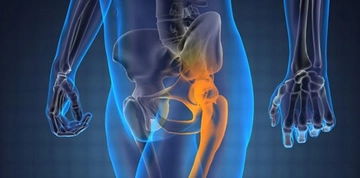

Diz ve Kalça Eklem Rahatsızlıkları İçin Öneriler

Diz ve kalça eklemlerindeki rahatsızlıklar için düzenli egzersiz yapmak, eklem hareketliliğini artırabilir. Yüzme gibi düşük etkili sporlar tercih edilebilir. Ayrıca, kilo kontrolü de eklemler üzerindeki yükü azaltarak daha az ağrı hissetmenize yardımcı olabilir.